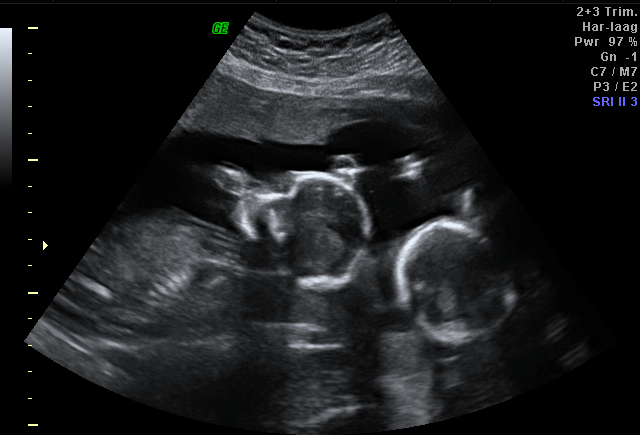

Mijn apparatuur geeft de beste kwaliteit 2D zwart-wit beelden, maar heeft ook de best mogelijke applicatie voor 3D & 4D (bewegende 3D beelden). Tijdens de echo kijk je mee op groter beeld en krijg je uitleg over wat we zien. Je mag filmen en foto’s maken zoveel als je wil. Je hebt de mogelijkheid om de opnames digitaal te ontvangen.

2D beelden:

Dit zijn de bekende zwart-wit beelden. Deze beelden worden ook gebruikt voor de medische echo’s bij de verloskundigenpraktijken. Hiermee kunnen we de baby vanaf al heel vroeg in de zwangerschap tot bijna het eind van de zwangerschap in beeld brengen. Met deze beelden bepalen we de ligging, kunnen we het hartje zien en ook beluisteren. Deze echo is geen gezondheidsverklaring voor de baby en geen garantie voor het verloop van de zwangerschap.

3D/4D beelden:

Het beeld is driedimensionaal. Dit geeft diepte, lengte, breedte en kleur op het scherm. Hierdoor kan je al wat uiterlijke kenmerken zien. Bolle wangetjes? Een klein wipneusje? Volle lipjes?

Bij bewegende 3D beelden spreken we van 4D. Je kunt het zien als een live opname. De mooiste beelden heb je tussen de 26 en 28 weken zwangerschap, maar ook deze beelden kunnen eerder en later in de zwangerschap gemaakt worden.

De kwaliteit van het beeld is van meerdere factoren afhankelijk: de hoeveelheid van het vruchtwater, de locatie van de placenta, de duur van zwangerschap, de dikte van de buikwand van de moeder en uiteraard de ligging van het kindje.